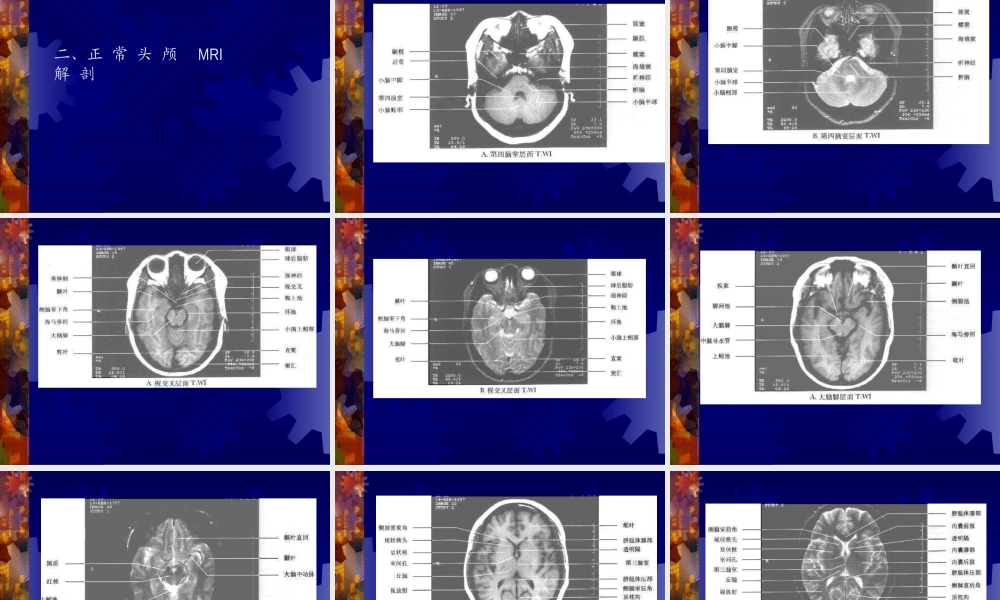

正常头颅CT及MRI解剖闫炳苍一、头颅CT正常解剖二、正常头颅MRI解剖三、脊柱的正常MRI解剖